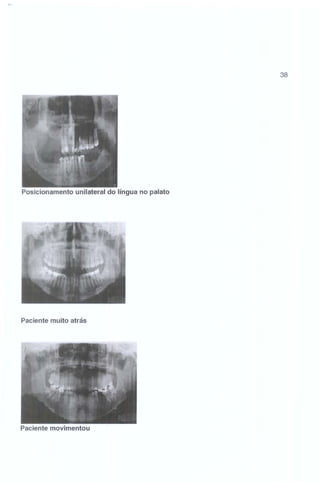

Posicionamento unilateral do língua no palato

Paciente muito atrás

Paciente movimentou